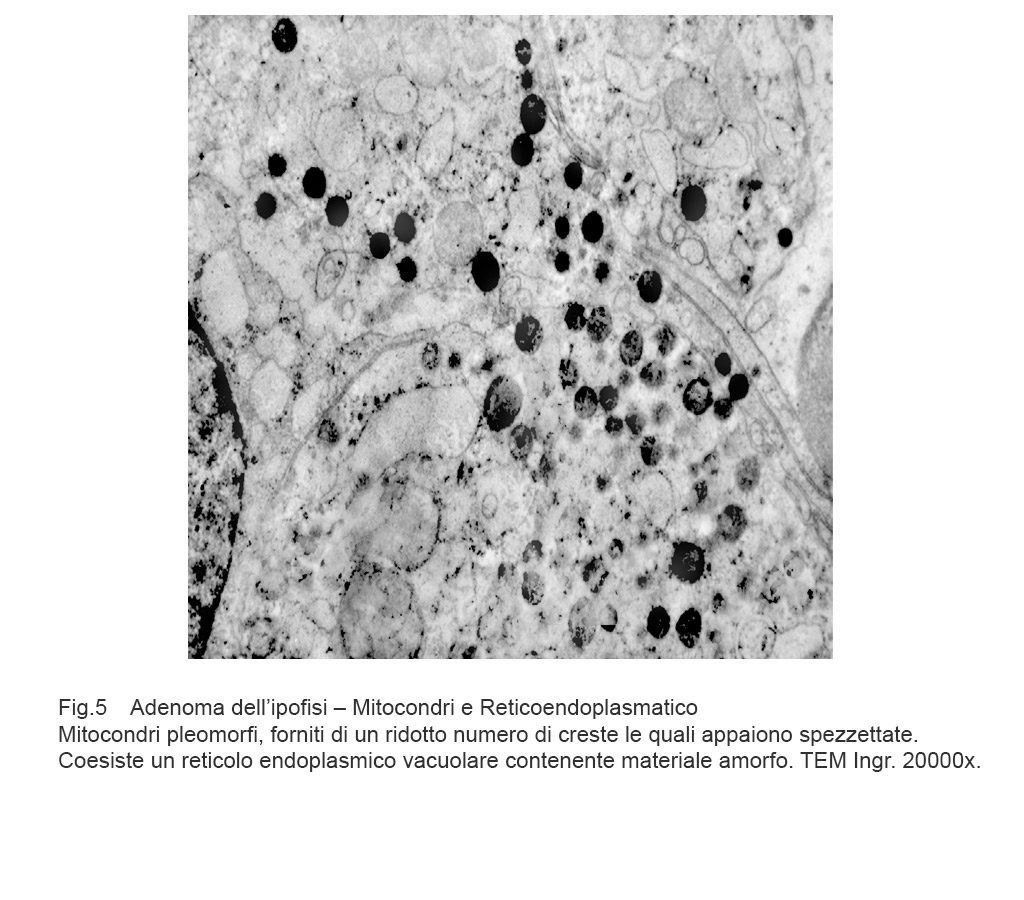

I dati rilevati possono essere sintetizzati nei seguenti punti descrittivi:

Mitocondri e R.E.: mitocondri con microvacuoli e depauperati di creste sono commisti a dilatazione micro-macrovacuolare del reticolo endoplasmico; alcuni di questi vacuoli sono occupati in modo parziale da materiale amorfo.

Fig.5  Fig.6